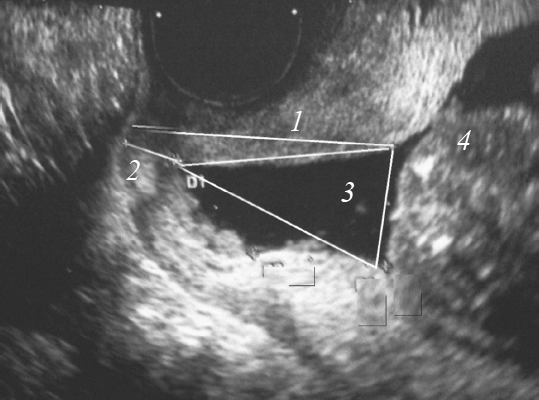

Материалы и методы. Изучено течение и исходы беременности у 164 женщин с ИЦН. Проведено компьютерное соматотипирование по Р.Н. Дорохову, измерение силы мышц тазового дна с помощью прибора pelvic muscle trainer.